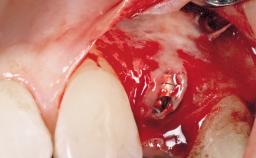

A 33-year-old female patient presented with an upper left central incisor that required extraction after a failed endodontic therapy. The tooth had been traumatized when the patient was a teenager and had undergone several endodontic treatments, including two apicectomy procedures. The patient was in good health and did not smoke. Clinical examination showed that the patient had a high lip line. In full smile, the gingival margins of the upper teeth were visible to the first molars. The gingival margins of central incisors 11 and 21 were only just showing. Examination of tooth 21 confirmed that the tooth was mobile and had hypererupted by 1 mm.

Placement Protocol Immediate implant placement

Tooth Site Maxillary incisor or canine

Socket Morphology Single-root socket

Socket Integrity Damage to one or more bone walls

Bone Volume Damage to one or more socket walls